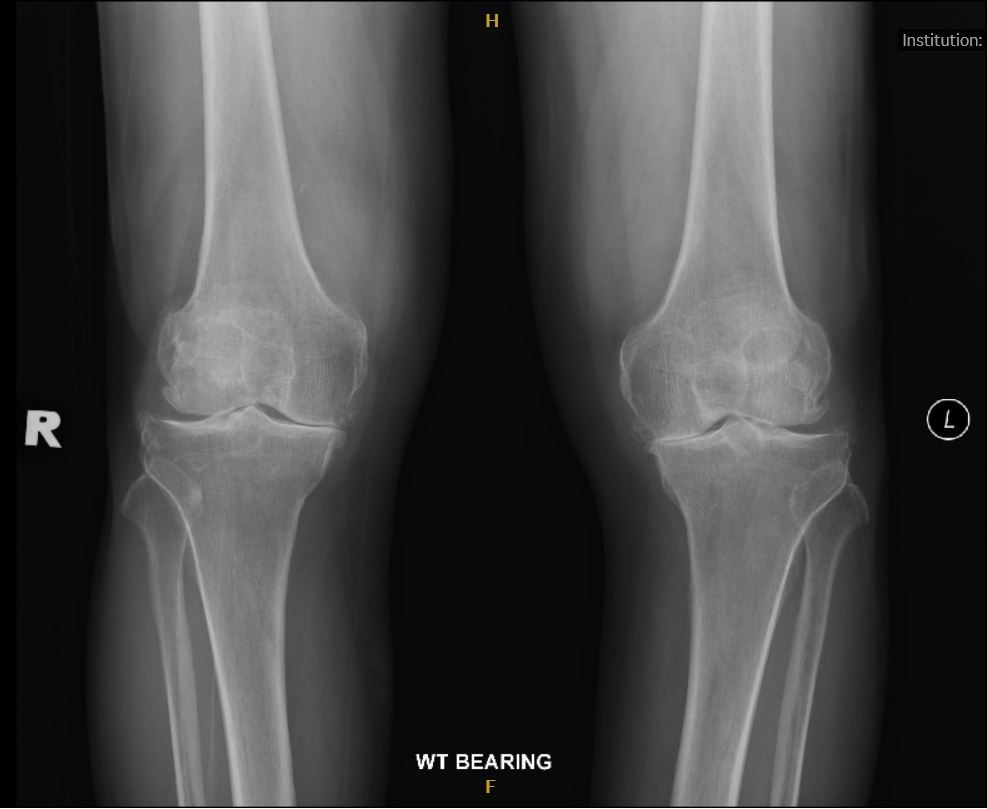

Q

Describe deformity seen. When performing TKR to either knees, how would you perform soft tissue balancing for correction of this deformity?

A

There is varus deformity, a coronal plane deformity.

There is concave (ST tight) and convex side (ST loose/strecthed).

Always start with tight side/ concave side first, which is medial side in this deformity.

Sequence of medial compartment release

1. Osteophytes

2. Deep MCL & Medial knee capsule

3. Posterior Medial Corner - capsule, semimembranosus.

4. Superficial MCL

i) Posterior oblique portion - if medial extension tightness

ii) Anterior portion - if medial flexion tightness

On this xray, there is valgus deformity in the coronal plane.

There is concave (ST tight) and convex side (ST loose/stretched).

Always start ST release at the tight side/ concave side first, which is lateral side in this deformity.